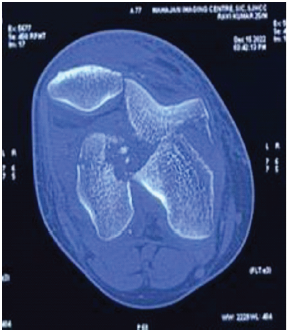

Isolated Double Hoffa Fracture of the Distal Femur without Intercondylar Extension: A Rare Case Report

Utkarsh Jain , Vipin Gupta , Navdeep Singh Keer

………………………………p.66-70